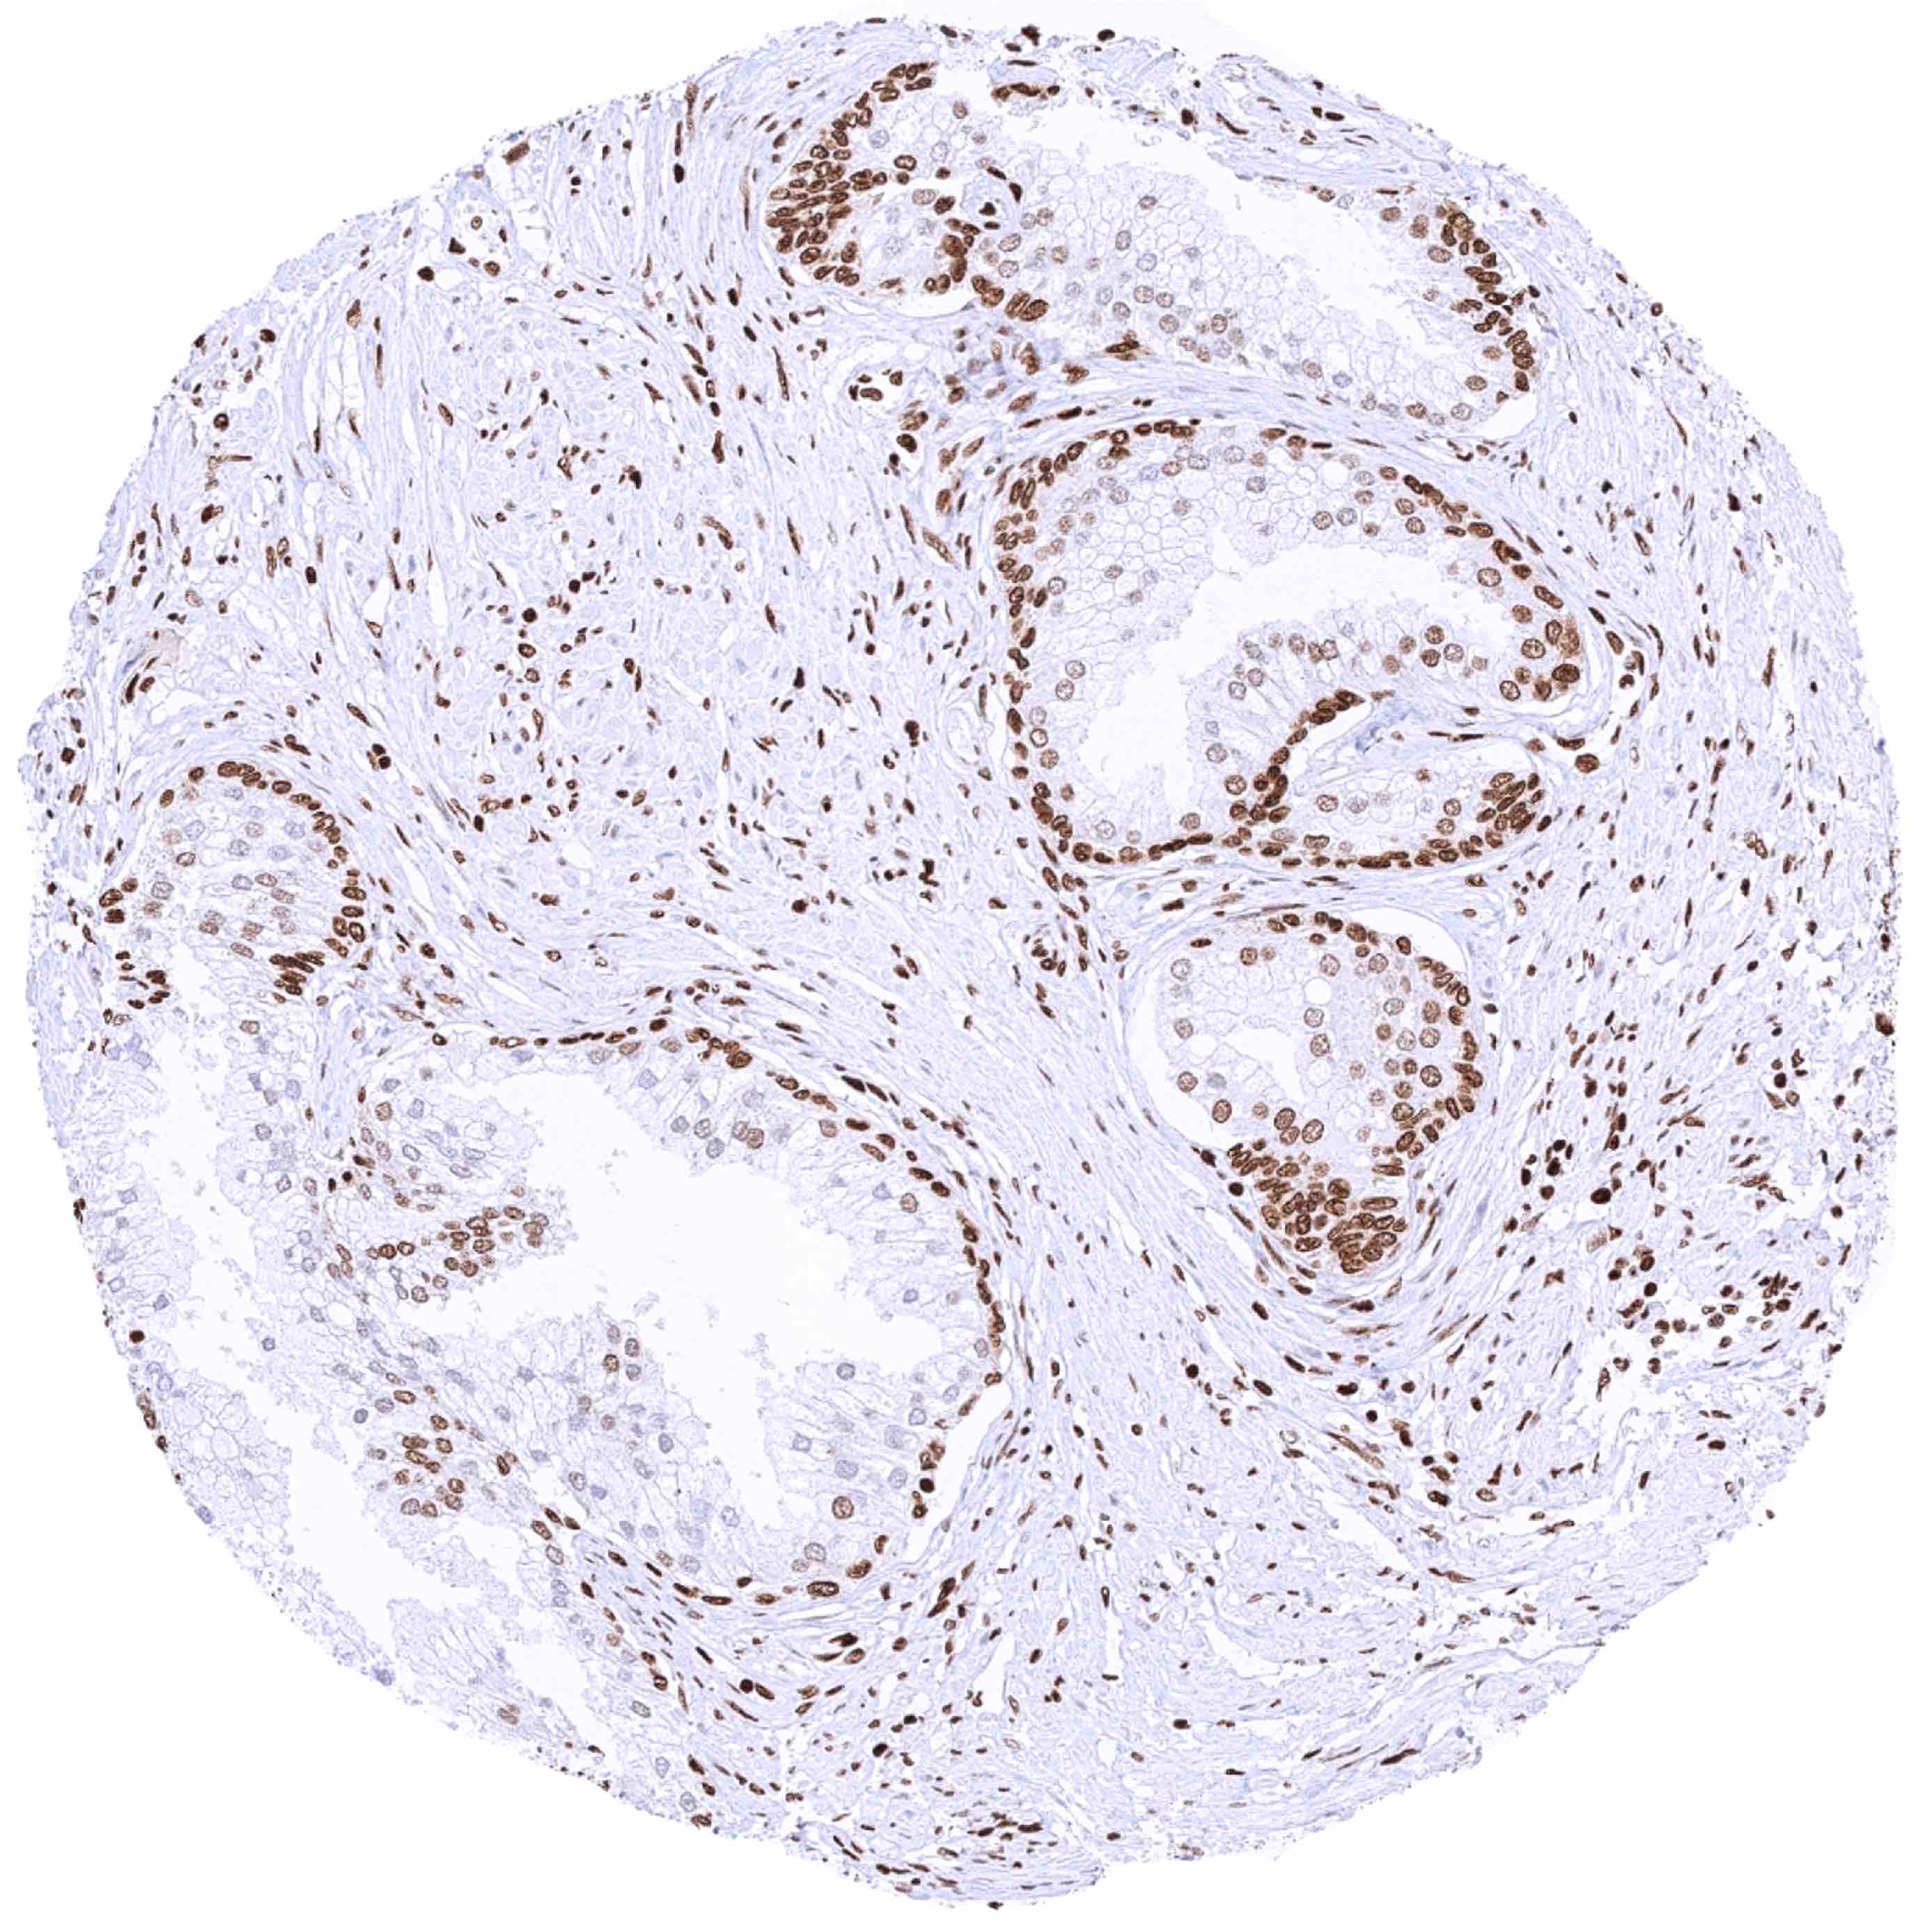

Prostate – Significant nuclear HMGB1 staining of all cells. Staining is particularly low in acinar cells and highest in basal cells